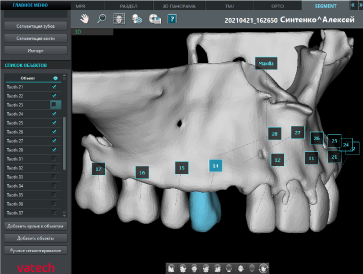

Сегментация зубов и костей

Автоматическое отделение зубов от костей и тела нижней челюсти от верхней челюсти выполняется модулем Segment. При необходимости данные о поверхности можно экспортировать* из программы Ez3D-i в виде отдельных файлов STL.

* При экспорте исследования в программу просмотра данные КТ записываются на диск вместе с моделями зубов и челюстей.

Сегментация зубов

Сегментация кости